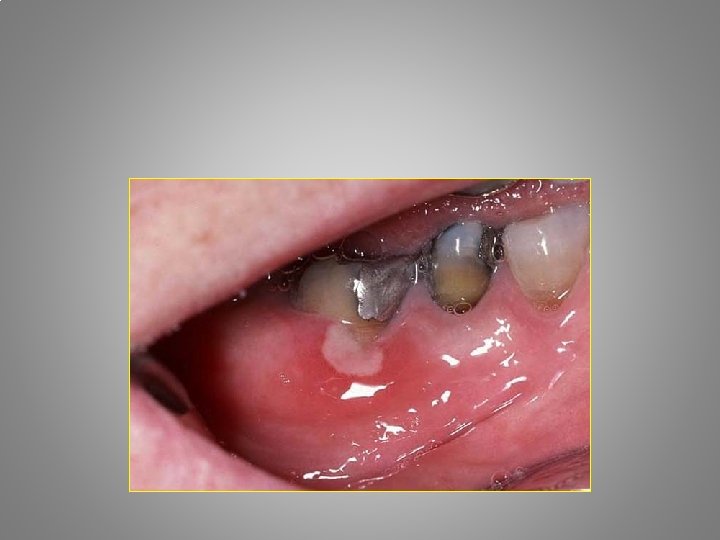

Types of orofacial pain Odontalgia : - Exposed dentin - Caries - Pulpitis - Apical periodontitis - Craced tooth sy. - Occlusal trauma - Periodontal abscessacute necrotising gingivitis - Periodontitis

Examination • Extraoral and intraoral inspectio. Signs of the inflammations. Tumor, calor, rubor, functio laesa. • Palpation of the laesion, lymphatic nodes, TMJ, periapical areas • Biting, cold, hot, percussion, bend forward

Caries Pain - food penetration - esthetic disorder - bad smell and taste - gingivitis Big lesion - X-ray, fiberoptic - change of tha approximal contour